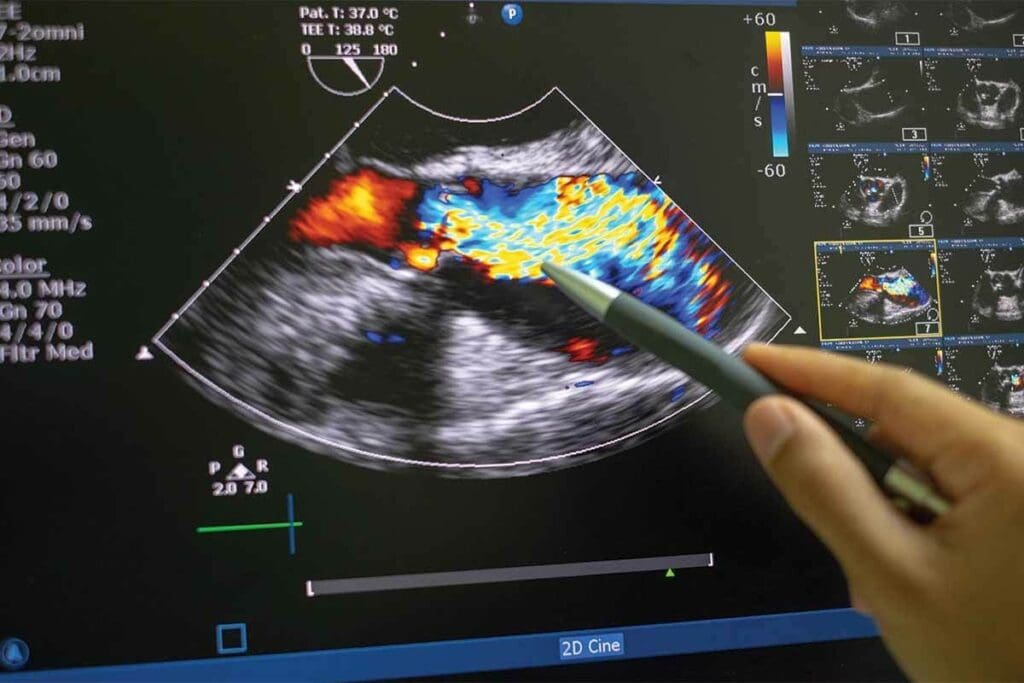

Echocardiogram: Ultrasound Imaging of the Heart

Echocardiograms are key in cardiology, using ultrasound to see the heart’s inside. This method is non-invasive and helps diagnose and track heart issues.

Types of Echocardiograms

There are many echocardiogram types, each for a different purpose. The most common ones are:

- Transthoracic Echocardiogram (TTE): This is the most common, where the probe is on the chest to get heart images.

- Transesophageal Echocardiogram (TEE): The probe goes into the esophagus for closer heart images, great for the back of the heart.

- Stress Echocardiogram: Done before and after stress (like exercise or medicine) to see how the heart works under stress.

What an Echocardiogram Reveals About Heart Function

An echocardiogram shows a lot about the heart’s shape and how it works. It can find:

- The heart’s size and shape, helping spot problems like hypertrophic cardiomyopathy.

- How well the heart valves work, spotting issues like stenosis or regurgitation.

- The heart’s pumping ability, helping diagnose heart failure.

Advantages and Limitations of Ultrasound Imaging

Echocardiography is non-invasive, doesn’t use radiation, and shows images in real-time. But, it depends on the operator and can be hard to see in some cases, like obesity or lung disease.